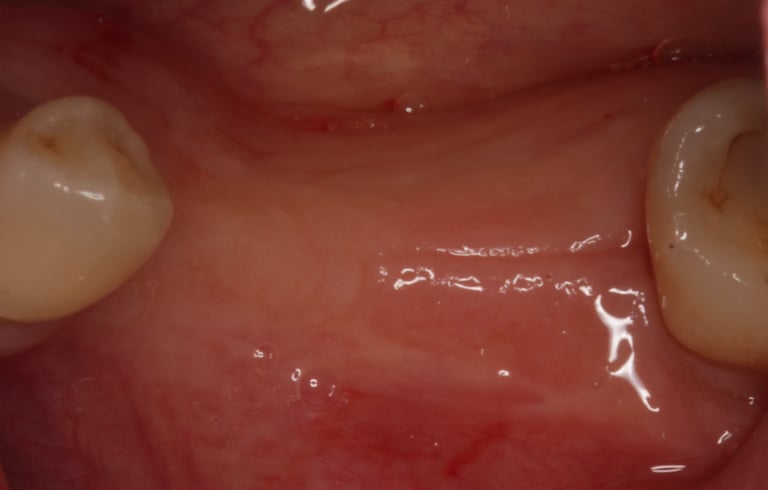

La phase préthérapeutique est clé pour identifier les facteurs de risque susceptibles d’influencer la cicatrisation, l’ostéointégration ou la durabilité de l’implant, et pour planifier une prise en charge parfaitement adaptée au profil de chaque patient.